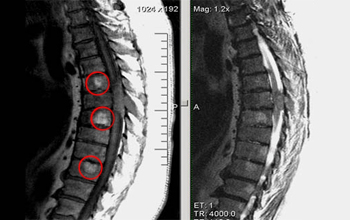

Определяет ли МРТ метастазы

При подозрении на метастазы делаются снимки соответствующих областей, в которых предполагаются дочерние уплотнения.

Метод информативен, помогает обнаружить малейшие разрастания, но для исключения ошибок вводится контрастное вещество. Это помогает обнаружить метастазы в следующих областях:

- В головном или спинном мозге — МРТ назначается при подтверждённой опухоли и наличии неврологических симптомов, расстройстве зрения, слуха, выпадении чувствительности.

Метастазы